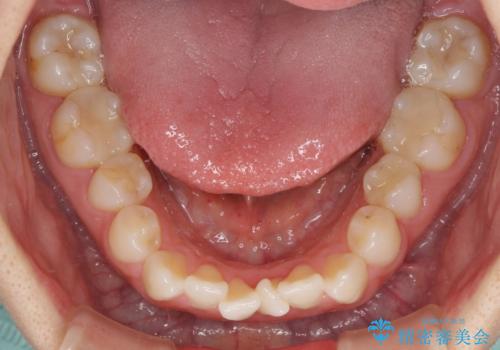

下顎前歯の叢生が顕著な場合、歯列改善後に歯と歯と歯肉の間にブラックトライアングルという隙間ができてしまいます。

軽減することはできますが、完全に解決することは矯正治療のみでは不可能なため、リスクとして事前に周知しておく必要があります。